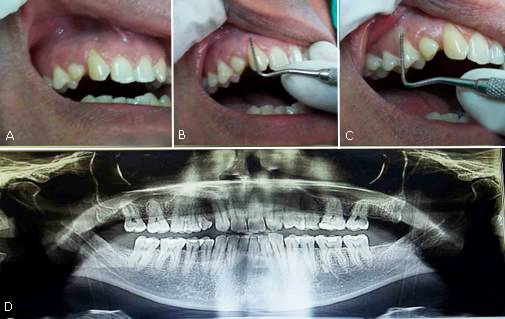

Paciente masculino, blanco, obrero, de 43 años de edad, que acude a consulta de Periodoncia de la Clínica Estomatológica “III Congreso del PCC” de Matanzas, Cuba, remitido del nivel primario de atención por retracción apical del margen gingival vestibular en 13, 53 y 14. Se confecciona historia clínica de la especialidad. Al interrogatorio, niega la existencia de antecedentes médicos personales y familiares de relevancia; refiere “cambio de posición de la encía en dichos dientes” que comenzó desde aproximadamente dos años y progresó en los últimos meses. Clínicamente existía ausencia clínica del 12, presencia del 53, exposición de la superficie radicular en 13, 53 y 14 por migración del margen gingival vestibular hacia apical del límite amelocementario, sin alcanzar la línea mucogingival (Fig. 1, A).

Con sonda periodontal de William se midió la profundidad del surco gingival de 13, 53 y 14; en todos fue 1 mm interproximalmente y 0 mm en caras libres. No se observó sangramiento al sondaje ni signos clínicos de inflamación, las papilas interdentales cubrían los nichos gingivales. Con pie de Rey marca NSK se midieron las coronas clínicas de los dientes afectados desde el margen gingival hasta el borde incisal u oclusal (15 mm la del 13; 7 mm la del 53 y 12 mm la del 14). La RP se midió con sonda periodontal, de la LAC al cenit gingival de cada diente (RP del 13= 5 mm, RP del 53= 3 mm y RP del 14= 4 mm) (Fig. 1, B y C). Encía adherida de 1,5 mm en 13 y 53 y 1 mm en el 14 (desde cenit gingival de dichos dientes a unión mucogingival) con pie de Rey.

Se indicó radiografía ortopantomográficala que mostró oligodoncia del 12 y 22, reabsorción radicular del tercio medio y apical del 53, sin pérdida ósea interproximal, ni áreas radiolúcidas laterales ni periapicales en los dientes con recesión. (Fig. 1, D).

Fig. 1 - A: Recesiones periodontales de 13, 53 y 14. B y C: Sondaje y medición de recesiones. D: Aspecto radiográfico de los dientes a tratar.